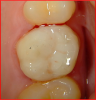

Fig 10. Post-treatment view of the molar that was restored using a universal composite and bioactive composite restorative. After composite placement, occlusion was adjusted, slightly into the cuspal contact.

Figure 10